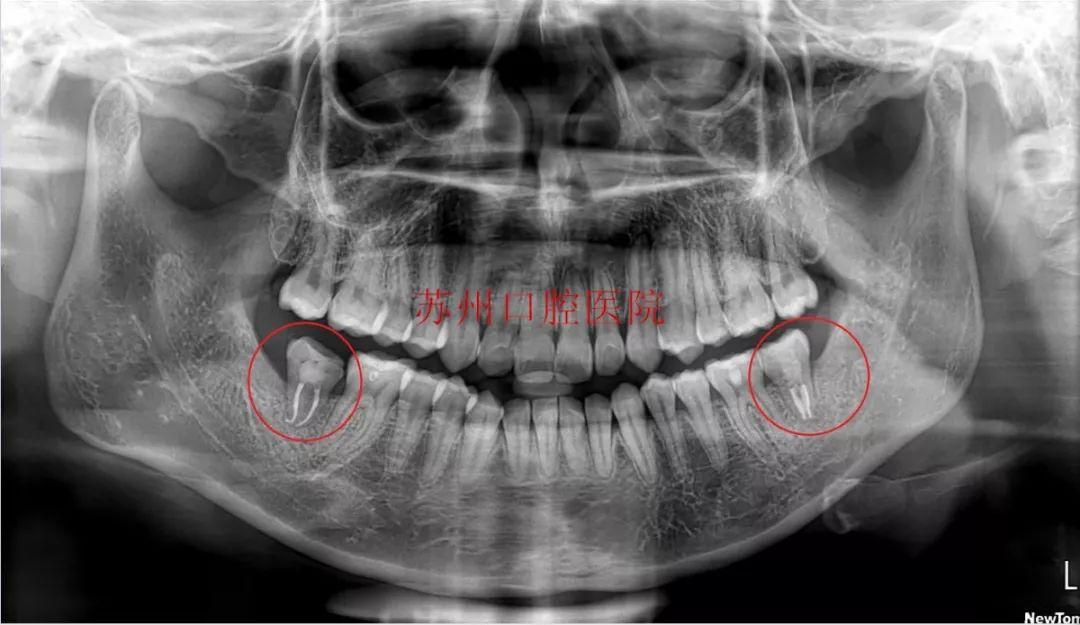

自體牙移植方案:通過預(yù)判評(píng)估,進(jìn)行了自體牙移植,在拔除齲壞患牙后,用自身的智齒替代被拔除的患牙行使功能,大限度地保留了天然牙,又避免了種植牙。

(智齒是口腔內(nèi)牙齒的“佳替補(bǔ)隊(duì)員”)